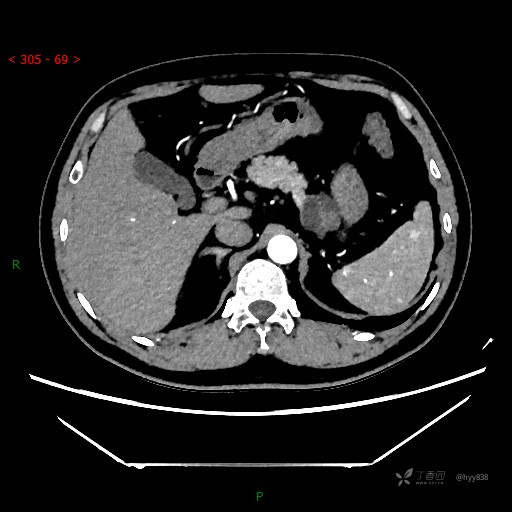

增强动脉期